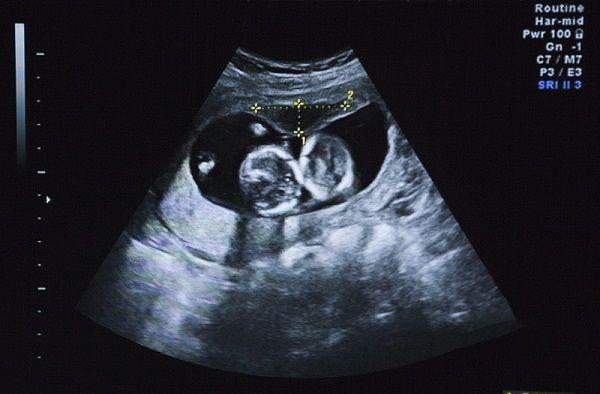

我怀孕有几个月,近期,查觉到胎儿有跳动的情况,但好像每一次的位置都不一样,在网上查阅了一些相关信息,有很多姐妹在说这种情况是胎儿在打嗝,而这个地方就可能是头或者是胸,你能告诉我怎么判断吗?

胎儿打嗝的地方一般来说,有很大的几率会是头部,但也不能绝对地说那个地方就是头部,如果在下腹部感觉到胎宝宝打嗝次数多的话,这种情况就很有可能胎位是正的,那么就可以高枕无忧了。

如果打嗝的位置在孕妈的肚脐以上的话,那么胎儿很有可能胎位不正,这个时候你就应该去医院检查身体情况了,并且要想办法,将胎位恢复正常,不然在生完孩子后,很有可能会出现婴儿生下来后就死掉的情况。

之前,你说你怀孕只有几个月,所以最好去医院检查一下,一般情况下,孕妇在35周以后才会出现胎宝宝打嗝的情况,而你怀孕出现这种情况过于太早,因此不排除身体的其它因素导致的。

看完你的回答后,我非常担心胎儿的健康,所以连夜就去医院做了一些检查,在与医生的交流中,他说我这种情况确实是胎宝宝打嗝,并且还给我聊了一些关于怎么判断位置是头还是胸的方法,说的方法与你说的大致相同,那么在这段时间我需要禁忌一些事项吗?